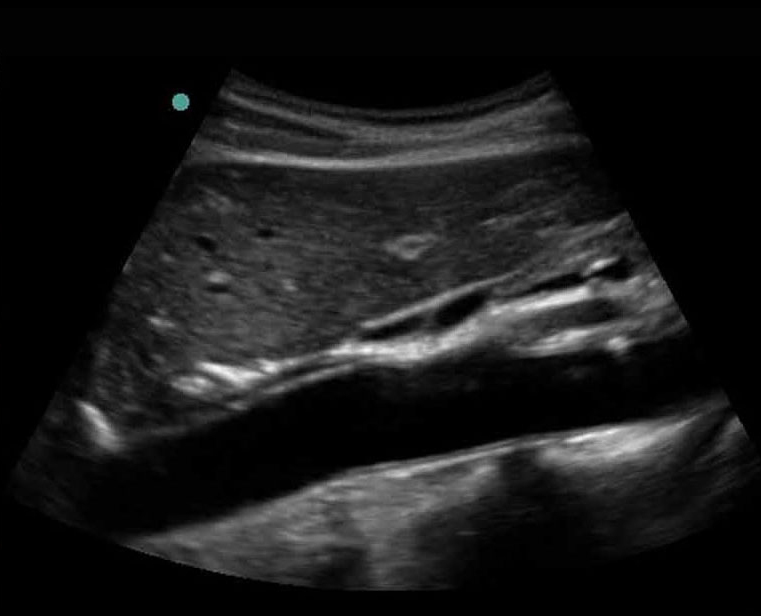

Imagen longitudinal proximal de la aorta